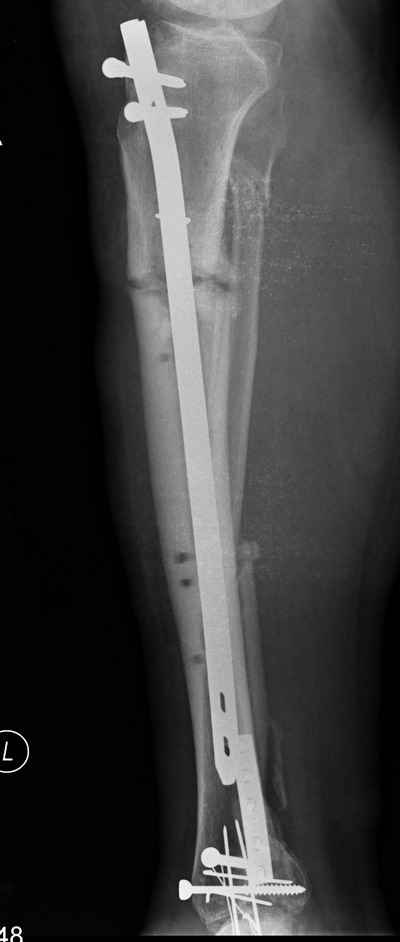

Необходимости в резекции кости нет. Мы бы убрали бы старый штифт и выполнили остеосинтез блокируемым штифтом с антибактериальным покрытием. Для этого бы использовали штифт для метаэпифизарных переломов с большим количеством блокирующих отверстий диаметром 8-9 мм, 1 дозу костного цемента, 4-5 г ванкомицина. Рассверлили бы костно-мозговой канал до 14-15 мм (желательно хорошо отмывать канал после рассверливания от обильной костной стружки, иначе эти мелкие кусочки кости после операции в течение длительного времени отходят через свищевые отверстия, являясь своего рода мелкими секвестрами и поддерживают воспаление в канале; для промывания мы устанавливаем в канал на всю длину толстый пластиковый жесткий желудочный зонд и промываем под напором из шприца Жане 2-3 литрами р-ра хлоргексидина). Установили бы штифт с покрытием в канал и блокировали через все отверстия для максимальной стабильности (толстый штифт с большим количеством винтов как никакой фиксатор обеспечивает столь важную для купирования воспаления стабильность). Один важный момент. В цементе напротив динамического отверстия следует делать такое же по форме овальное отверстие, для возможности динамизации в последующем.

2) Концы отломков нежизнеспособны. Надежды на надежное сращение нет. Необходима резекция.

В подобной ситуации бы сделали резекцию, остеотомию, наложили бы спице-стержневой аппарат в один этап. После окончания дистракции в аппарате при отсутствии признаков воспаления - остеосинтез обычным блокируемым штифтом, при воспалении в области спиц и стержней - штифтом с антибактериальным покрытием.